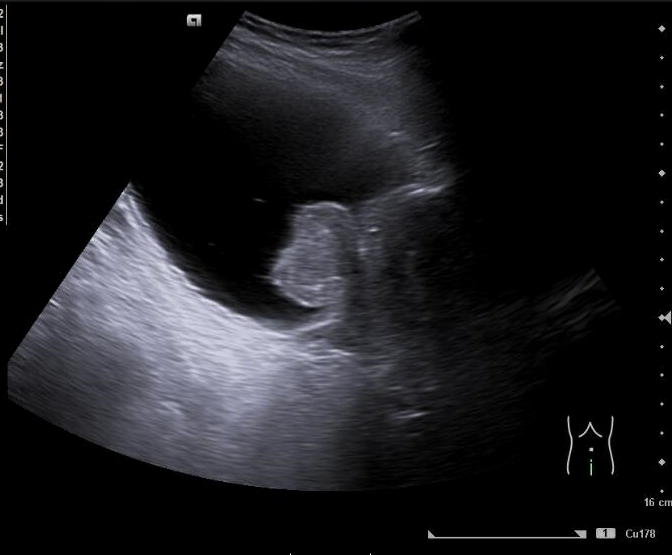

Imagen 4. Ecografía de vejiga y próstata: Corte sagital. Vejiga distendida con paredes engrosadas. Crecimiento del lóbulo medio prostático que impronta en vejiga. Volumen aproximado de 127 cc.